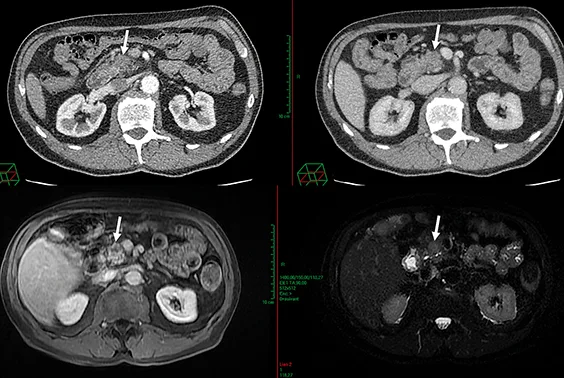

Figure 1 : AP résécable. Absence de contact veineux. Tumeur peu hypodense en scanner ayant nécessité un complément de documentation pancréatique par IRM

Figure 2 : AP isthmique, résécable d’emblée selon la définition du NCCN, présentant un contact veineux < 180°

Figure 3 : AP borderline artériel. Envahissement veineux (VMS) < 180° et artériel (AMS) < 180°

Figure 4 : AP localement avancé non résécable. Envahissement du TC > 180° et de l’AMS < 180°